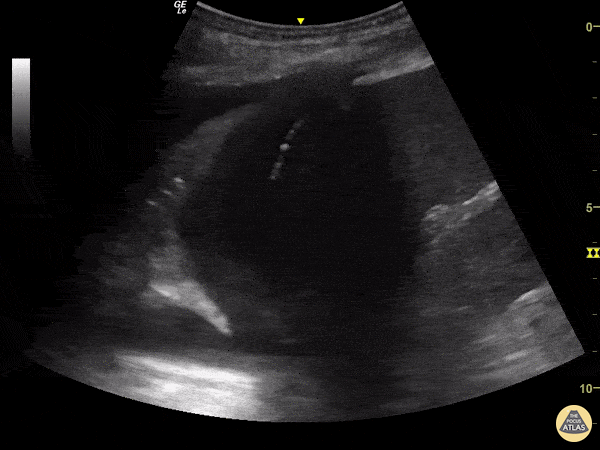

Pulmonary - Jellyfish Sign

This a PLAPS-point view located slightly above the diaphragm. This window is a key component of lung ultrasound evaluation for pleural effusion. This image reveals what is know as "Jellyfish Sign,” or consolidated lung floating in anechoic fluid (pleural effusion). Also note the static air bronchograms within the lung parenchyma. Renato Tambelli, Emergency Physician from Emergency Department of Marilia Clinics Hospital - Sao Paulo/ Brazil @R_Tambelli